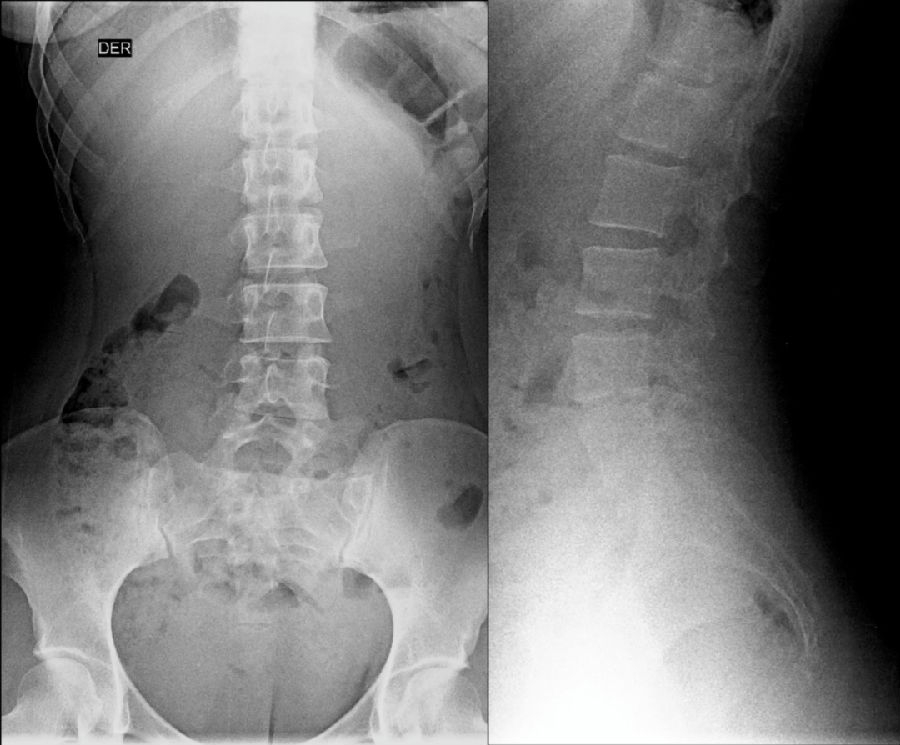

腰椎骶化及骶椎腰化均是椎骨发育的异常,腰椎骶化是指第五腰椎外型类似骶椎形态,并构成骶骨块的一部分,一侧或两侧横突肥大呈翼状,与骶骨发生融合或形成假关节。骶椎腰化是指第一骶椎演变成腰椎样形态,即第一骶骨从筋骨块中游离出来形成第6个腰椎。

如何在临床阅片准确判断是一个很重要的问题,这里介绍一个最准确的判断方法

这是一个最关键和准确的鉴定方法,国内著名骨放射学家杨世埙教授指导过,只要大家留意关注腰椎横突"三长/四翘/五宽",L3横突是最长的,L4横突是上翘的,L5横突最宽,特别用在胸椎腰化合并L5骶化的时候比较实用。

目前,腰骶移行椎以Castellvi的分类方法最为常用。其主要根据横突形态及其与骶骨、髂骨是否融合或形成假关节而分为4型,Ⅰ、Ⅱ、Ⅲ型又根据单、双侧分为A、B两个亚型。

III型:单侧(IIIa)或双侧(IIIb)腰椎完全骶化,腰5横突与骶骨完全骨性融合

L5右侧横突肥大与骶骨发生骨性融合,为Ⅲa型

L5双侧横突与骶骨骨性融合,为Ⅲb型

IV型:一侧为II型即腰5横突与骶骨形成假关节,对侧为III型即腰5横突与骶骨形成骨性融合

IV型即混合型:L5双侧横突肥大,一侧与骶骨相接触为Ⅱ型表现,另一侧与骶骨形成骨性融合为Ⅲ型